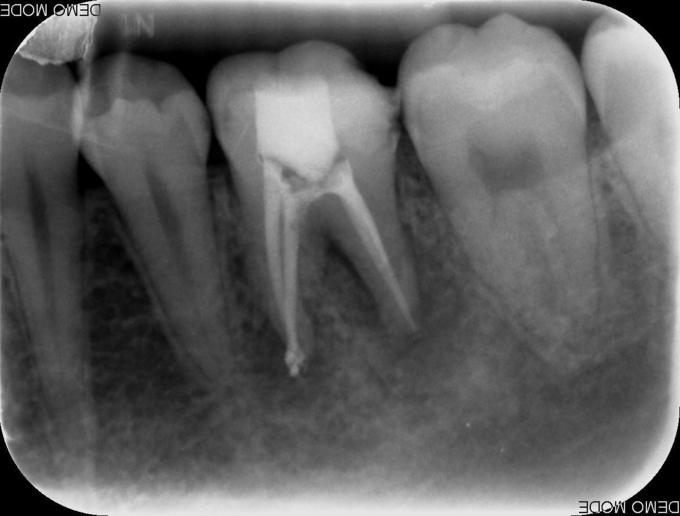

主诉:左下后牙咬物不适半年余 现病史:患者自诉半年年前左下后牙开始出现咬物不适,无自发痛、夜间痛,无放射到颌面部,今至我科就诊要求治疗

检查:#36 he 面见白色充填物,叩(+),松(-),咬合痛,冷热测无反应,电测无活力,牙龈稍红肿。余牙未见明显异常 X线示:#36根尖周有阴影

诊断:#36慢性根尖周炎 治疗:#36开髓、揭顶,拔髓,冲洗,测量WL,根管预备,封Ca(OH)2两周,ZOE暂封。两周后复诊去暂封,冲洗根管,测WL,试尖,根充。